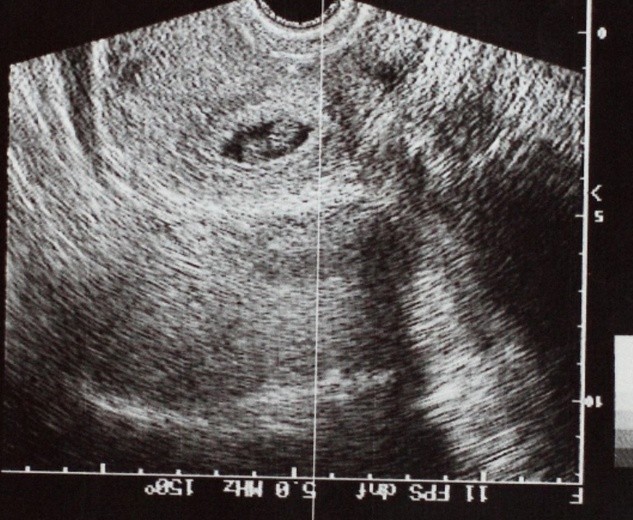

W „Gazecie Wyborczej” z dnia 6 września br. jest artykuł Pana Sławomira Zagórskiego pt. „Zdrowsze dzieci z zamrożonych zarodków?”. W artykule tym omawiany jest problem zamrażania ludzkich embrionów w ramach procedury zapłodnienia pozaustrojowego (zapłodnienia in vitro). Autor informuje że według opinii lekarzy wykonujących zapłodnienie in vitro w Anglii, bezpośrednie wszczepianie embrionów matce w cyklu miesięcznym kiedy pobrano od niej komórki jajowe po tzw. stymulacji hormonalnej, a więc wtedy kiedy podając kobiecie dużą dawkę hormonów spowodowano dojrzewanie licznych komórek jajowych w jednym cyklu miesięcznym, jest bardzo ryzykowne dla płodu. Natomiast zamrożenie wytworzonych sztucznie w probówce embrionów i rozmrożenie ich po miesiącu dla wszczepienia do jamy macicy niesie mniejsze ryzyko dla płodu.

Autor słusznie stwierdza, że w cyklu miesięcznym, kiedy pobrano komórki jajowe po stymulacji hormonalnej śluzówka macicy jest hormonalnie zmieniona, co szkodzi płodowi. Jednak sugestia, że zamrażanie ludzkiego embrionu w ciekłym azocie jest korzystne zdrowotnie dla płodu, jest absurdem. Po prostu miesiąc po pobraniu komórek jajowych od kobiety, śluzówka jej macicy jest mniej niebezpieczna dla płodu, natomiast ryzyko zdrowotne płodu związane z zamrożeniem embrionu jest duże, choć być może mniejsze od ryzyka związanego ze wszczepieniem embrionu w zmienionej hormonalnie macicy. Zwykle znaczna ilość sztucznie wytworzonych i następnie zamrożonych embrionów nigdy nie zostanie wszczepiona do jamy macicy i zostaną one w przyszłości zniszczone.